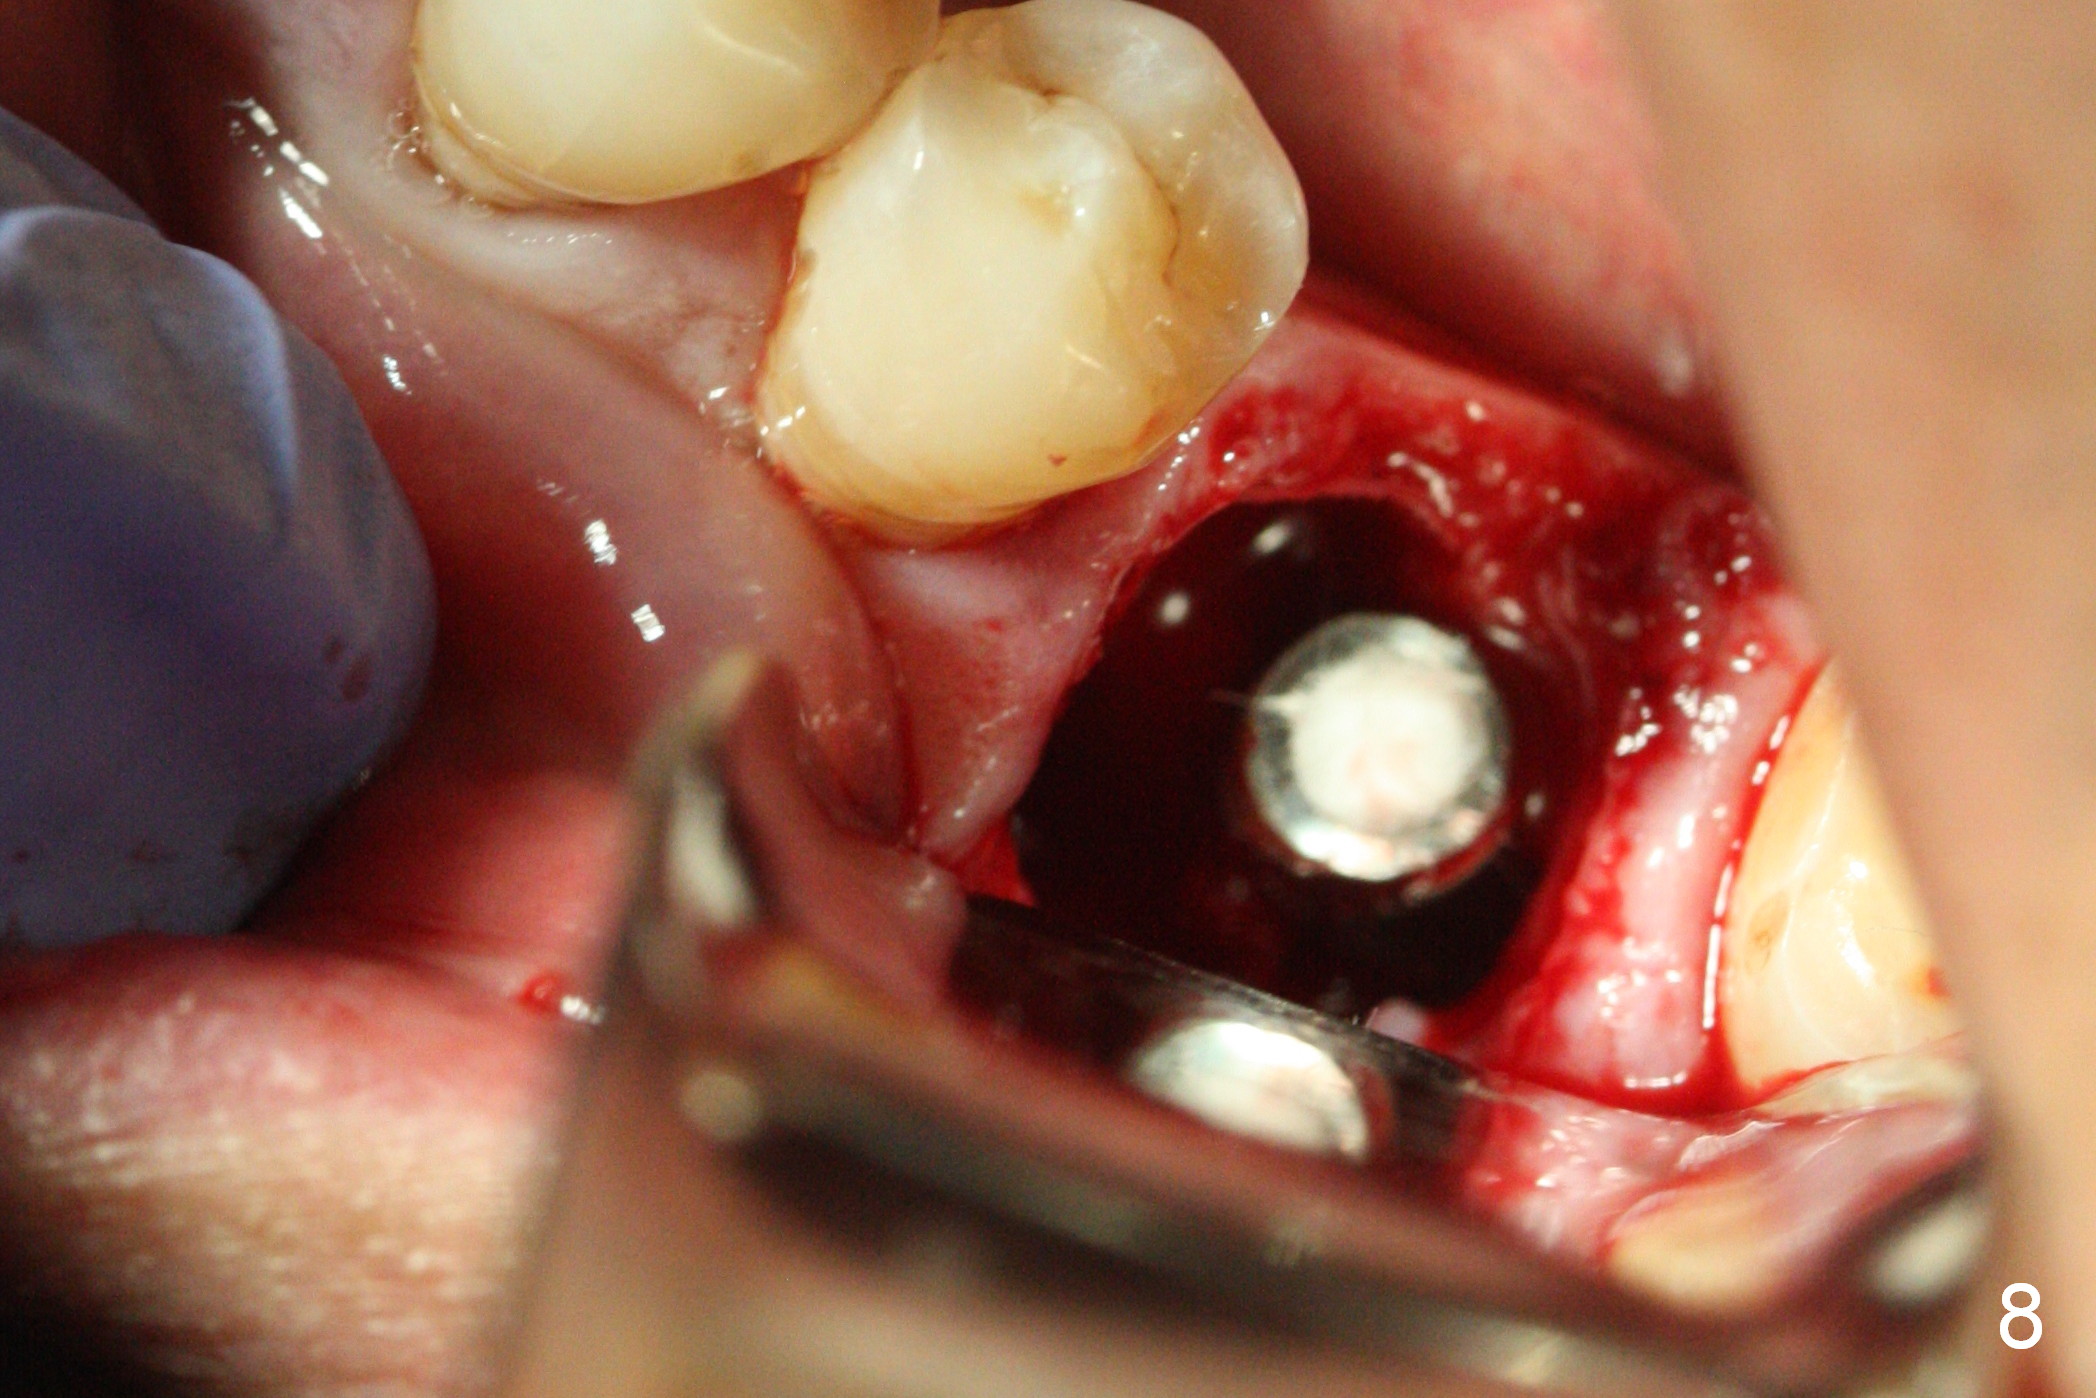

The asymptomatic tooth (#19) has a midbuccal fistula (Fig.1 <). The mesiobuccal pocket is 10 mm with purulent discharge from the sulcus (Fig.2,3). The mesiobuccal wall defect is confirmed when the tooth is extracted. Osteotomy is initiated lingually in the septum following septal crestoplasty (flattening) (Fig.4: using 1.6 mm drill for 9 mm). Since the lingual portion of the osteotomy is higher, it is difficult to use drill with stopper. For the narrow septum osteotomy, multiple drills are used sequentially (Fig.5 after 4.3 mm drill). A 4.5x11 mm dummy implant is placed (Fig.6) apparently too deep. When a 5x11 mm IBS implant is being placed, the depth is tightly controlled (Fig.7). The implant is apical to the lingual crest, whereas there is ~ 2 mm implant exposure buccally. That is, there is a large gap mesiobuccally (Fig.8), which is filled with .5-1.5 mm allograft (Fig.9 *). A 6.5x5.7(3) mm abutment (A) is placed and trimmed for an immediate provisional (Fig.10 P). The lacerated buccal gingiva is sutured as well as application of Perio Glue.